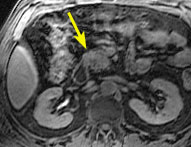

In this sub-second coronal T2-weighted image, there is a solid mass in the head of the pancreas (arrow).